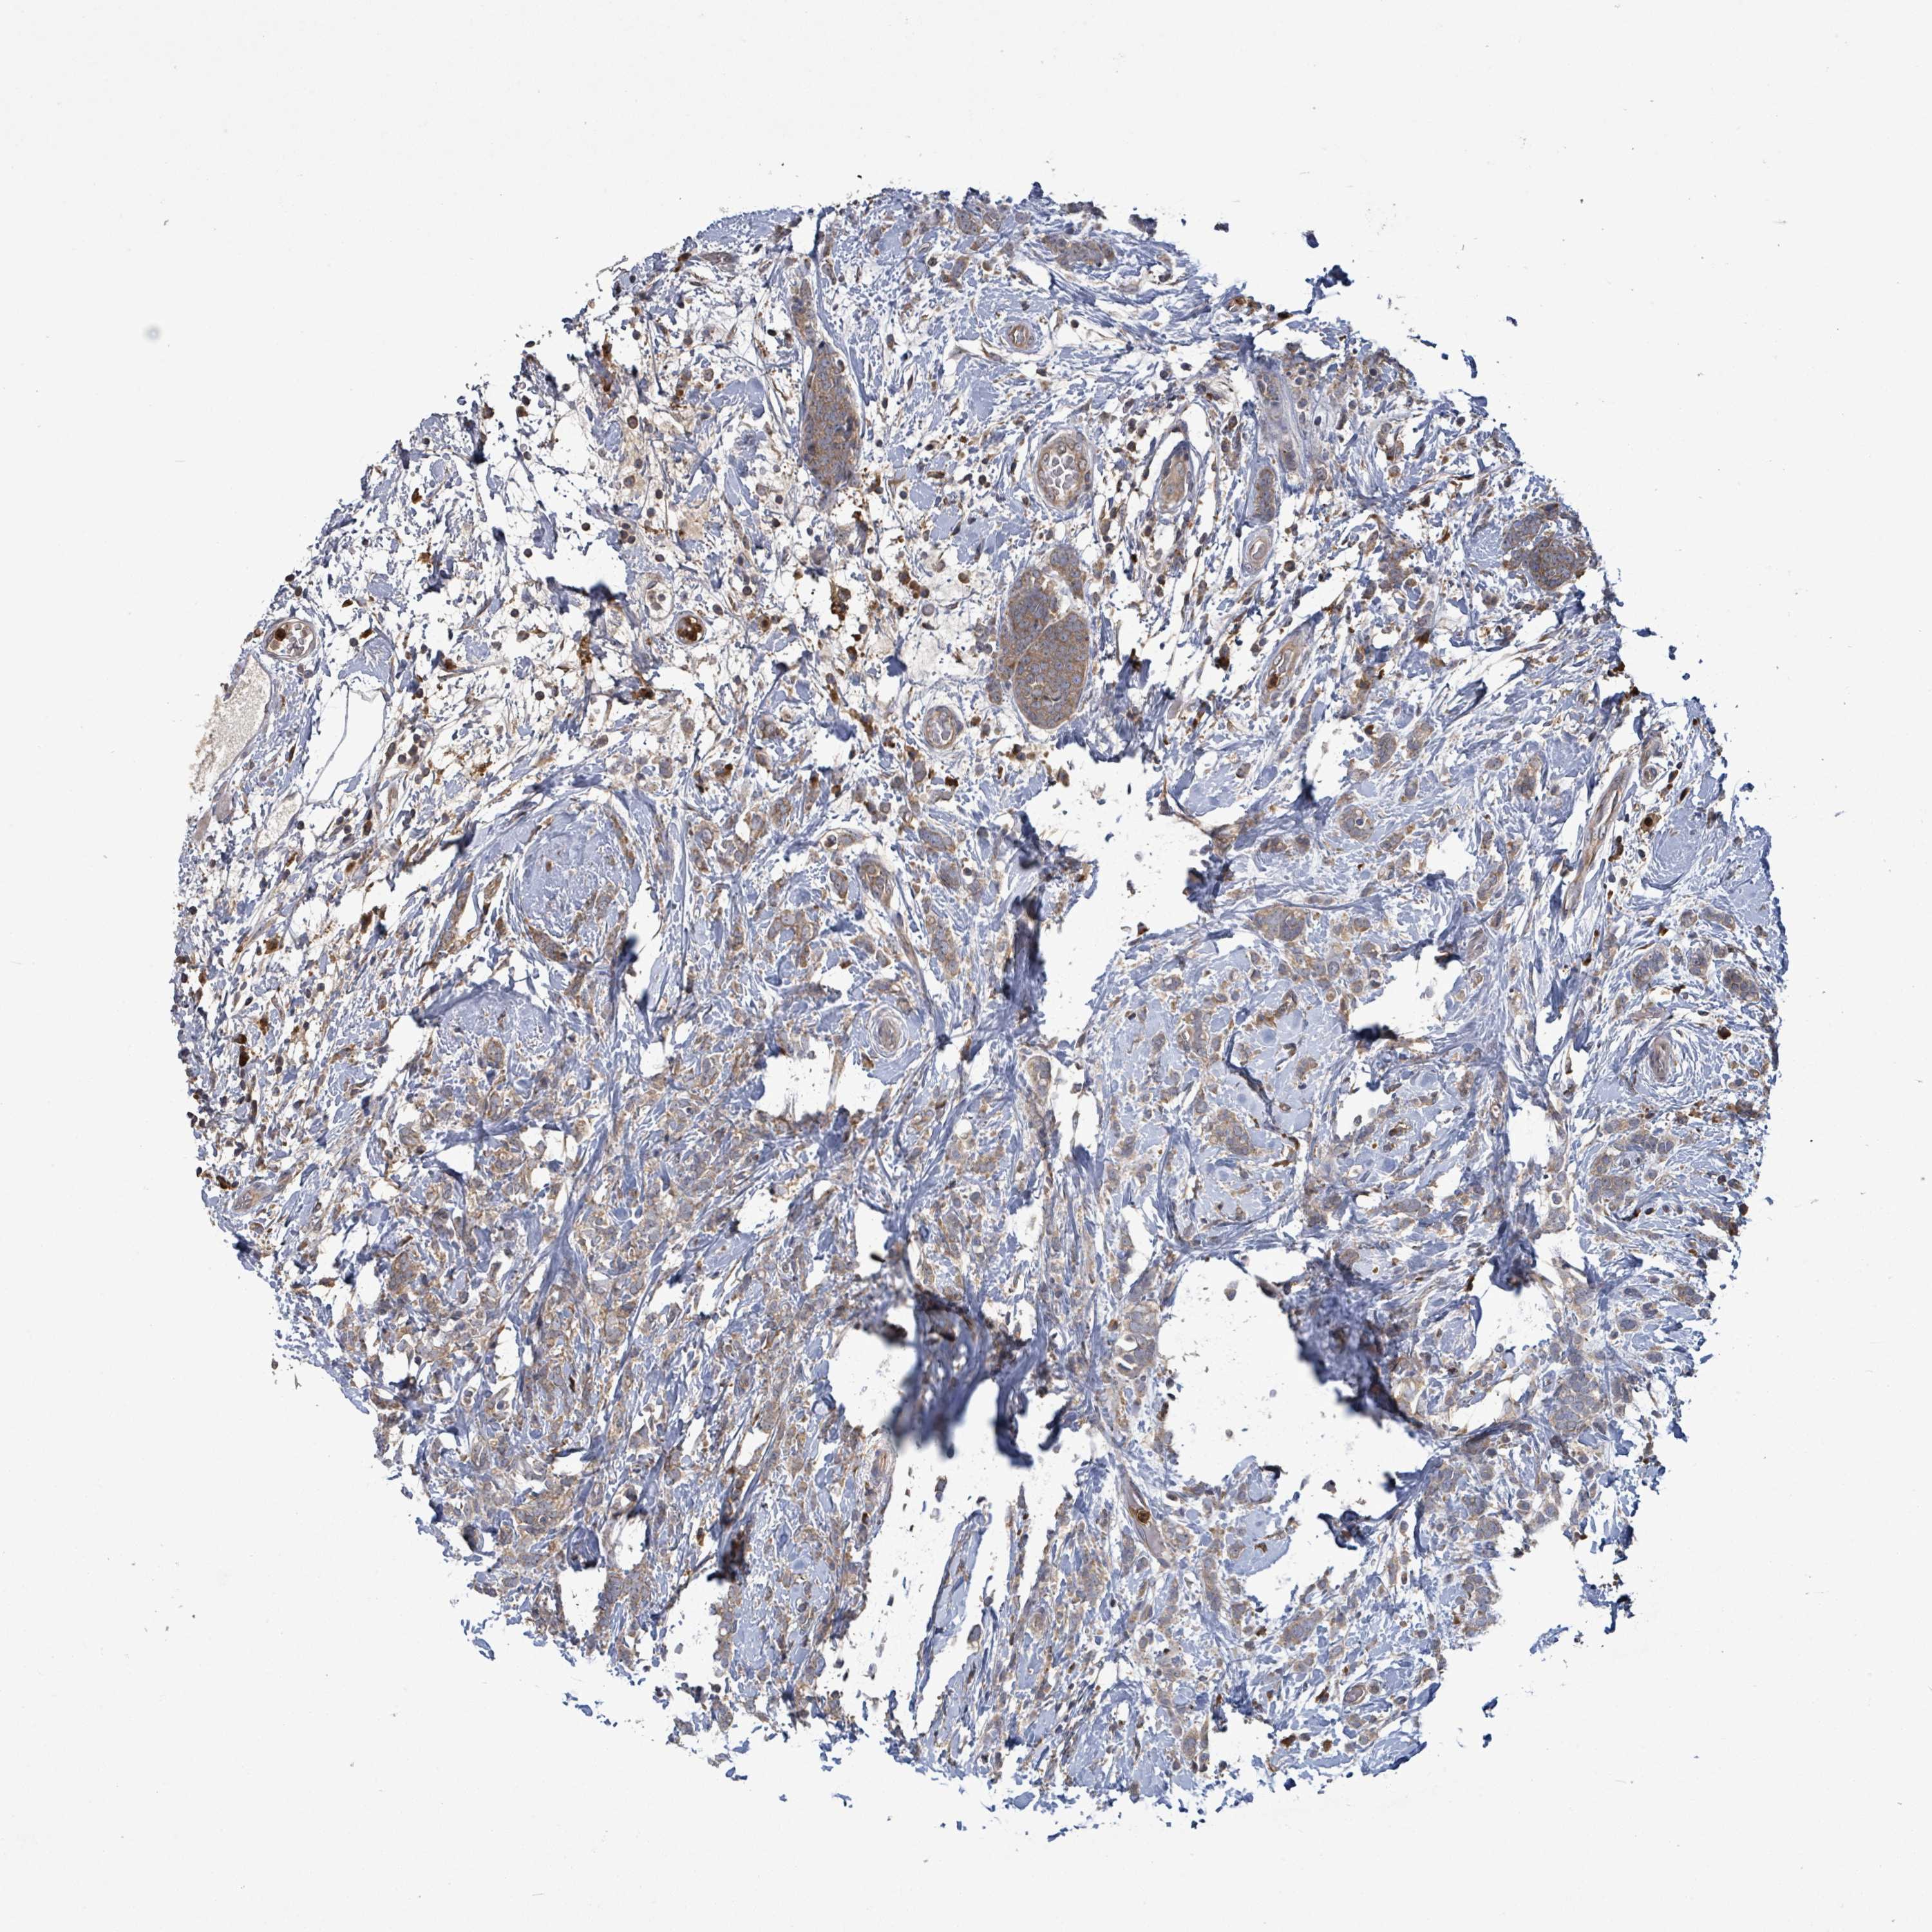

BRCA TCGA BRCA VALIDATION PROTEIN EXPRESSION

ANTIBODIES

AND

VALIDATION